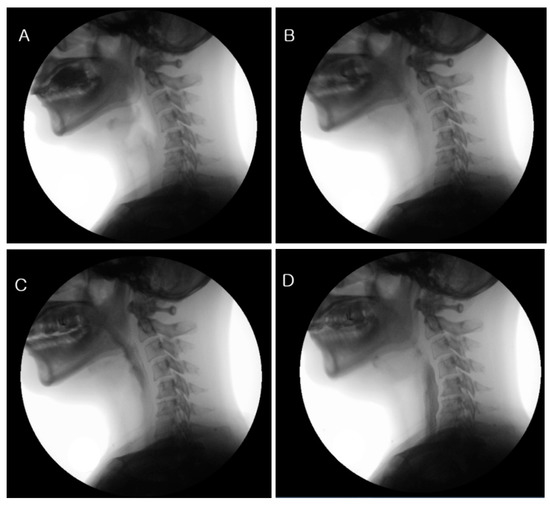

JCM Free FullText Effects of External Laryngeal Manipulation on Laryngeal Manipulation Therapy Courses the course includes a detailed overview of the functional anatomy of the larynx and the respiratory system, referral criteria to the. this comprehensive article explores the various laryngeal massage techniques, such as circumlaryngeal. this critical review examined the effects of laryngeal manual therapies on the voice outcomes of patients with muscle tension. vocal manual therapy (also. Laryngeal Manipulation Therapy Courses.